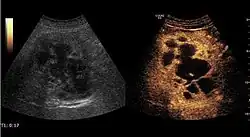

It is the most common liver tumor with a prevalence of 0.4 – 7.4%. It is generally asymptomatic but also can be associated with pain complaints or cytopenia and/or anemia when it is very bulky. It is unique or paucilocular. It can be associated with other types of benign liver tumors. Characteristic 2D ultrasound appearance is that of a very well defined lesion, with sizes of 2–3 cm or less, showing increased echogenity and, when located in contact with the diaphragm, a "mirror image" phenomenon can be seen. When palpating the liver with the transducer the hemangioma is compressible sending reverberations backwards. Doppler exploration reveals no circulatory signal due to very slow flow speed. CEUS investigation has real diagnosis value due to the typical behavior of progressive CA enhancement of the tumor from the periphery towards the center. The enhancement is slow, during several minutes, depending on the size of hemangioma and on the presence (or absence) of internal thrombosis. During late (sinusoidal) phase, if totally "filled" with CA, hemangioma appears isoechoic to the liver. Deviations from the above described behavior can occur in arterialized hemangiomas or those containing arterio-venous shunts. In these cases, differentiation from a malignant tumor is difficult and requires other imaging procedures, follow up and measurements of the tumor at short time intervals.[4]

Focal nodular hyperplasia